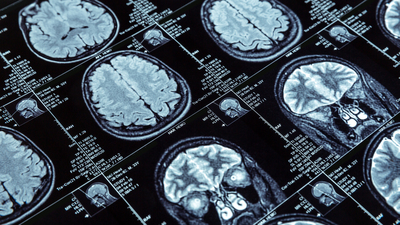

Türk Nöroloji Derneği Başkanı Prof. Dr. Mehmet Akif Topçuoğlu, beynin Covid-19'dan diğer organlara göre daha az etkilendiğini belirterek, "Bugüne kadar çok vaka gördük. Eğer beyin üzerinde sık görülen, hepimizi korkutacak ciddi bir etkilenim olsaydı şimdiye kadar belirtileri de fazlasıyla görülürdü. Çok şükür bu yok" dedi.

Covid-19'u ağır geçiren hastalarda bütün vücut gibi beynin de bu süreçten etkilendiğini ama farklı şiddetli hastalıklarda da aynı durumun görülebildiğini belirten Topçuoğlu, "Beynimizdeki 86 milyar nöron içerisinde Covid-19'un içeriye girişini sağlayacak reseptörler bulunmuyor. Fakat virüs, bu bölgedeki damarlar ve destek hücrelerinde bulunabiliyor. Dolayısıyla beyin indirekt şekilde etkileniyor ama beyin iltihabı ve diğer açılardan bir etkilenme söz konusu değil" dedi.

Topçuoğlu, Covid-19'un beyin üzerinde uzun dönemli, kalıcı hasarlara yol açıp açmayacağının tıp çevrelerince hala tartışıldığını, net bir kanıya henüz varılamadığını anlatarak, şunları kaydetti: "Şu anda ibre, Covid-19 açısından beynin, akciğer gibi diğer organlara göre biraz daha şanslı olduğu, beynin bu süreçten daha düşük düzeyde etkilendiği yönünde. 2 yıldır pandeminin uğultusu altında yaşıyoruz, bugüne kadar çok vaka gördük. Eğer beyin üzerinde sık görülen, hepimizi korkutacak ciddi bir etkilenim olsaydı şimdiye kadar belirtileri de fazlasıyla görülürdü. Çok şükür bu yönde belirtiler yok."